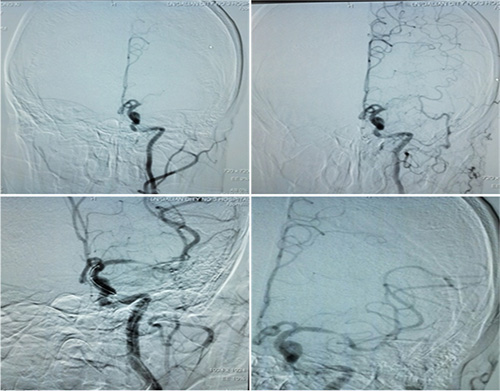

“时间窗和组织窗该相信谁?”经验丰富的张静波主任对该患者进行及时的CT灌注成像检查,结果显示灌注缺血区与核心梗死的不匹配,意味着患者还有可以挽救的脑组织,值得进行介入取栓治疗。取栓后,患者脑血管实现完全再通。

▲取栓前后对比图:患者脑血管实现再通